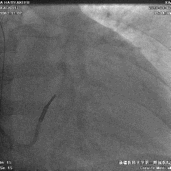

冠状静脉造影

● 十极标测电极进入窦口后总是超选小分支,进入过程中逆向旋转十极标测电极,顺利避开小分支开口,进入主干,造影显示可用后静脉和侧静脉各一个

鞘中鞘超选靶血管

● 使用鞘中鞘超选入靶血管造影,明确靶血管远端情况。

植入左室电极

● 首选后静脉,通过鞘中鞘递送左室电极,深插鞘中鞘作支撑,电极始终无法送达远端,考虑患者血管狭窄导致,更换靶血管,从侧静脉递送电极至远端。